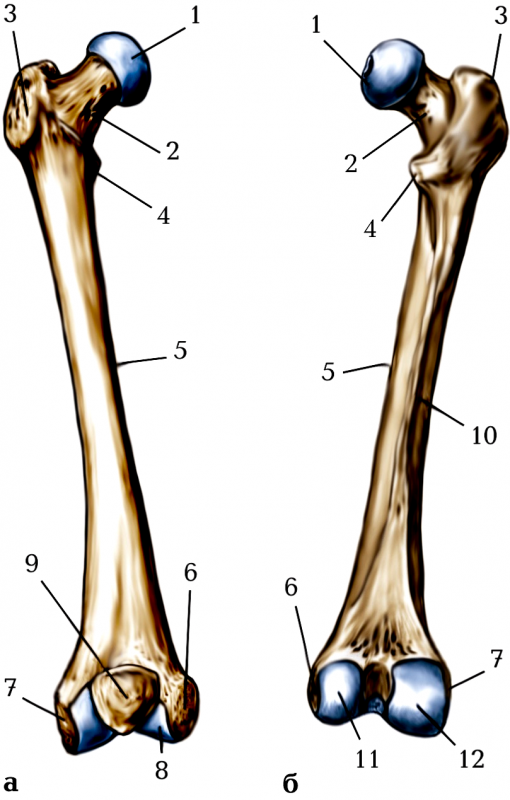

ЯКОЮ ЦИФРОЮ ПОЗНАЧЕНИЙ ВЕЛИКИЙ ВЕРТЛЮГ? (В АКУШЕРСТВІ ВИМІРЮЮТЬ ВЕРТЛЮГОВУ ДИСТАНЦІЮ).

варіанти відповідей

2

6

7

3

4

11

12

ЩО ІЗ ПЕРЕРАХОВАНОГО МАЄ FEMUR НА ПРОКСИМАЛЬНОМУ ЕПІФІЗІ?

2 ВИРОСТКИ

2 НАДВИРОСТКИ

ВЕЛИКИЙ ВЕРТЛЮГ

МАЛИЙ ВЕРТЛЮГ

ТУПИЙ ШИЙКО-ДІАФІЗАРНИЙ КУТ